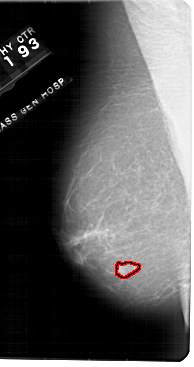

FILE: A_1948_1.LEFT_MLO.OVERLAY

TOTAL_ABNORMALITIES 1

ABNORMALITY 1

LESION_TYPE MASS SHAPE IRREGULAR MARGINS ILL_DEFINED

ASSESSMENT 4

SUBTLETY 3

PATHOLOGY BENIGN

TOTAL_OUTLINES 1

BOUNDARY